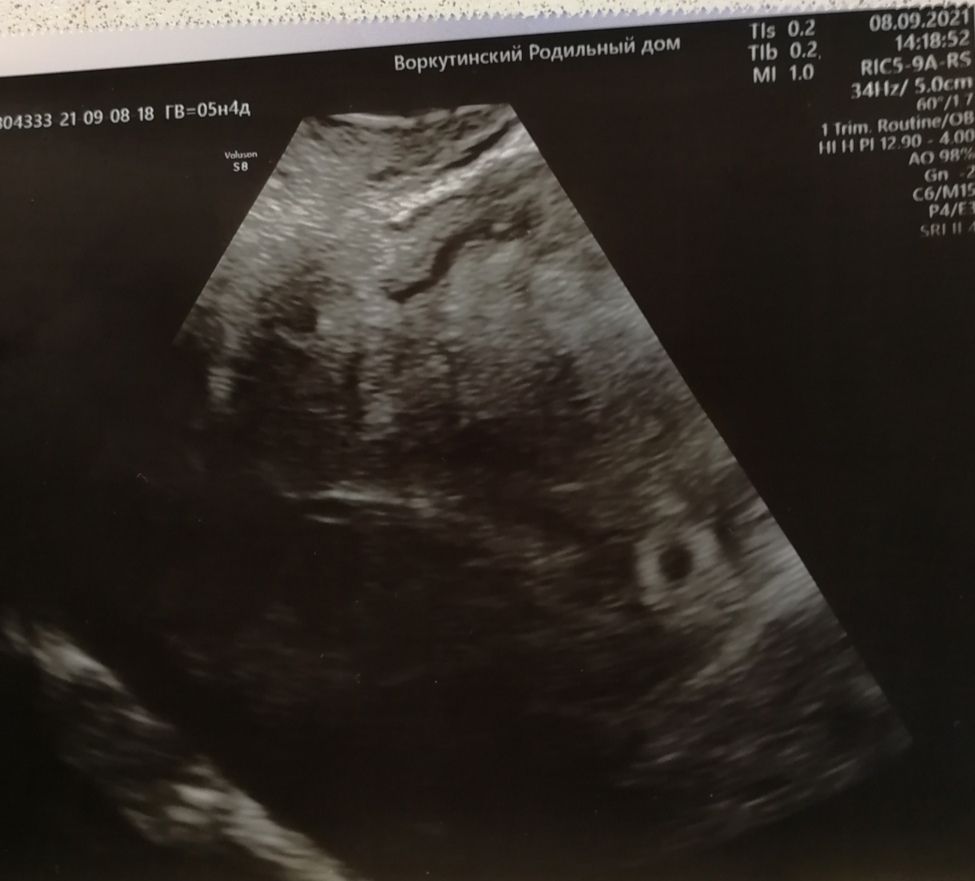

Тоже видели 2 ПЯ, второе, типа, поменьше, послабее, но в итоге идин эмбрион все же был. Так и не узнала, было это второе ПЯ или что то другое.